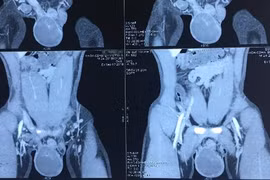

Bé 3 tuổi đã ung thư tinh hoàn, cha mẹ cần chú ý kiểm tra khi trẻ mới sinh

Phát hiện sớm, can thiệp kịp thời tinh hoàn ẩn, có thể giúp trẻ tránh được những biến cố lớn trong tương lai.